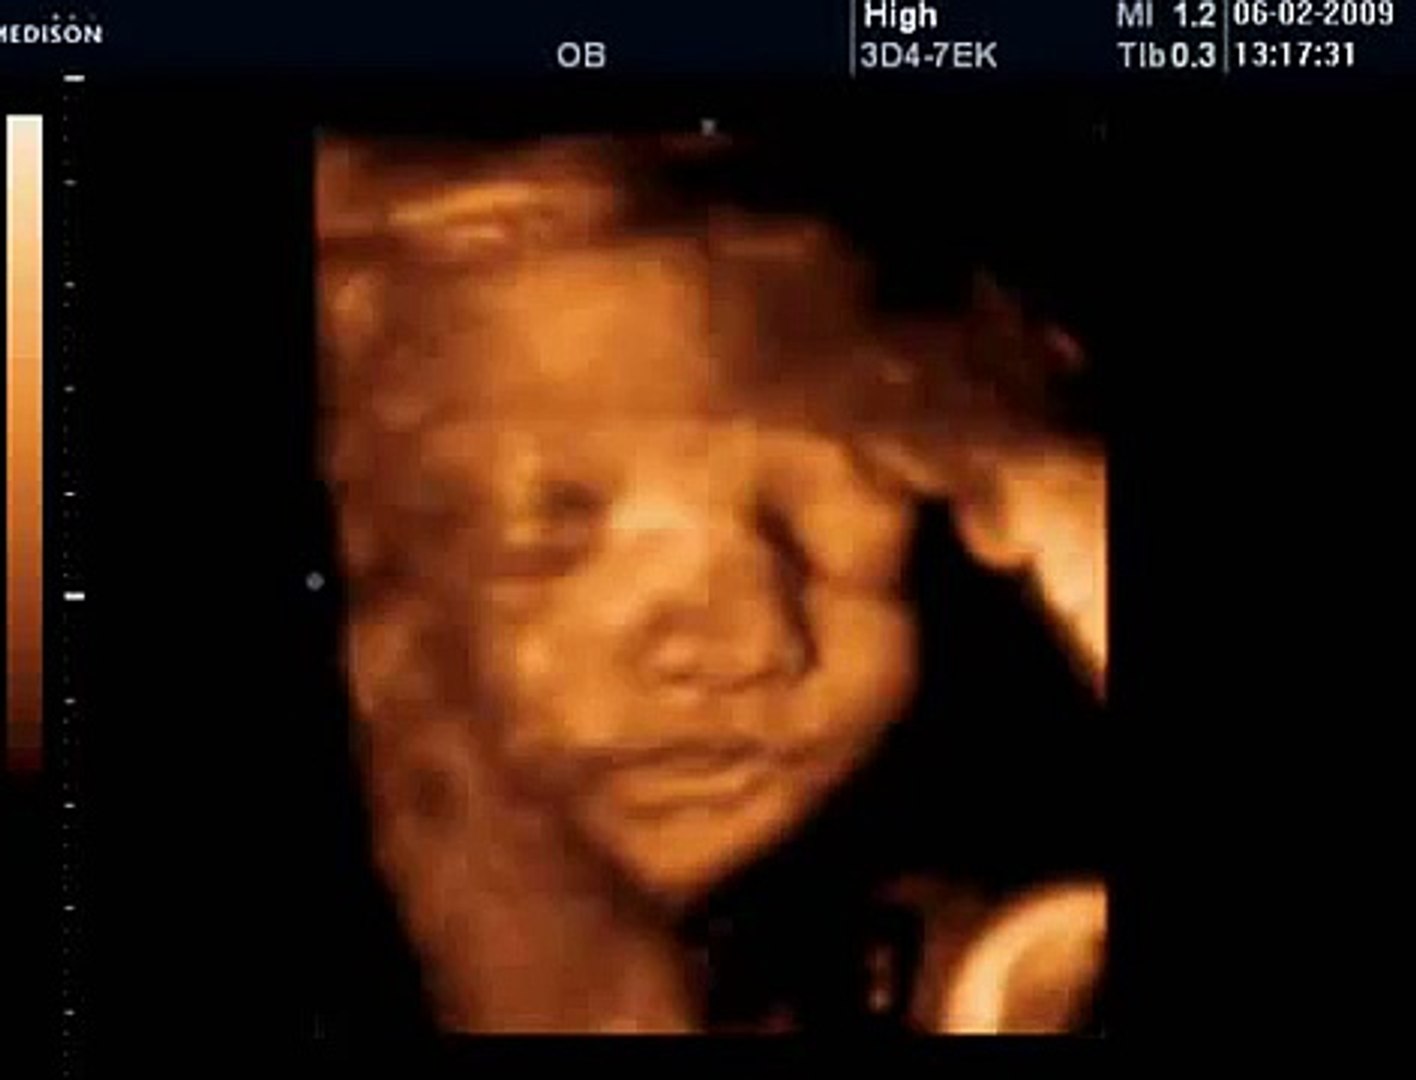

17 Haftalık Bebek Ultrason Görüntüsü

17 Haftalık Bebek Ultrason Görüntüsü.